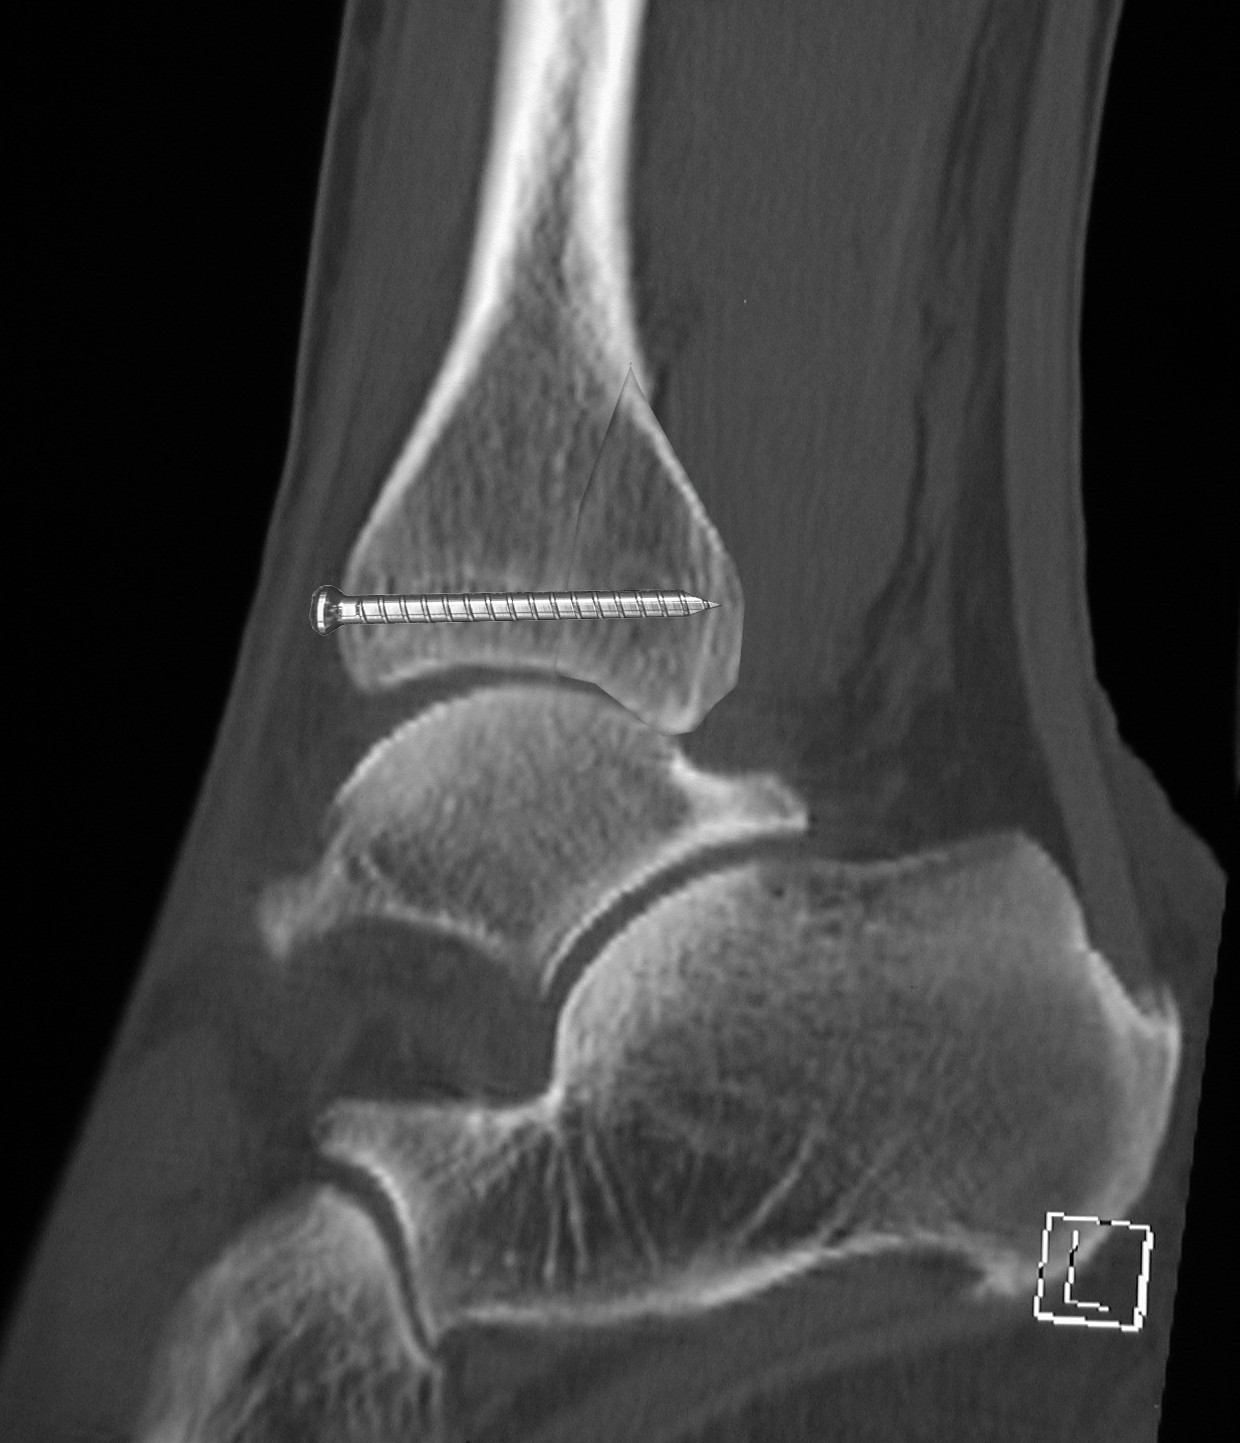

Hier spielt die Stellschraube eine besondere Rolle: Sie wird ausschließlich dann eingesetzt, wenn die Syndesmose tatsächlich verletzt ist oder nach einer Syndesmosennaht zusätzlich stabilisiert werden muss. Die Stellschraube ist also kein "einfaches" Osteosynthese‑Element, sondern ein deutlicher Hinweis auf eine behandlungsbedürftige Syndesmoseninstabilität – und damit auf eine deutlich reduzierte frühe Belastbarkeit.

Häufig wird die Stellschraube eingesetzt, weil sie die Malleolengabel zuverlässig komprimiert und die Position der Fibula sichert. Damit ist aber gleichzeitig festgelegt, dass das Gelenk rotatorisch blockiert bleibt. Für deine spätere Behandlung bedeutet das, dass Belastungssteigerungen erst nach gesicherter knöcherner Heilung und – bei Stellschrauben – nach deren Entfernung möglich sind. Die operative Versorgung ist also nicht nur ein chirurgischer Eingriff, sondern ein funktioneller Hinweis darauf, wie vorsichtig du im Verlauf sein musst.

Damit wird die Stellschraube zum zentralen Indikator. Eine Stellschraube bedeutet immer: Die Syndesmose war verletzt und ist nicht primär stabil. Sie dient dazu, Tibia und Fibula während der Heilung in korrektem Abstand und Rotation zu fixieren. Das Gelenk ist damit zwar rekonstruierbar, aber biomechanisch blockiert. Solange die Stellschraube eingesetzt ist, darf keine Rotation im OSG stattfinden. Dies macht jede Form der Vollbelastung riskant, auch wenn die Patientin subjektiv wenig Schmerzen angibt. Belastung erfolgt hier nicht nach Gefühl, sondern definiert: typischerweise 10–20 kg Teilbelastung bis zur Schraubenentfernung oder bis zur ärztlichen Freigabe.

Zusätzlich relevant für die Frage der frühfunktionellen Therapie ist die Versorgung der Syndesmose. Hier musst du zwischen starrer und dynamischer Stabilisierung unterscheiden. Eine Stellschraube fixiert Tibia und Fibula in einer stabilen, aber unphysiologisch starren Position. Rotation bleibt vollständig blockiert, und die Belastung ist klar begrenzt – typischerweise 10–20 kg Teilbelastung bis zur Schraubenentfernung oder ärztlichen Freigabe. Diese starre Stabilität erzwingt eine sehr vorsichtige Belastungsprogression.